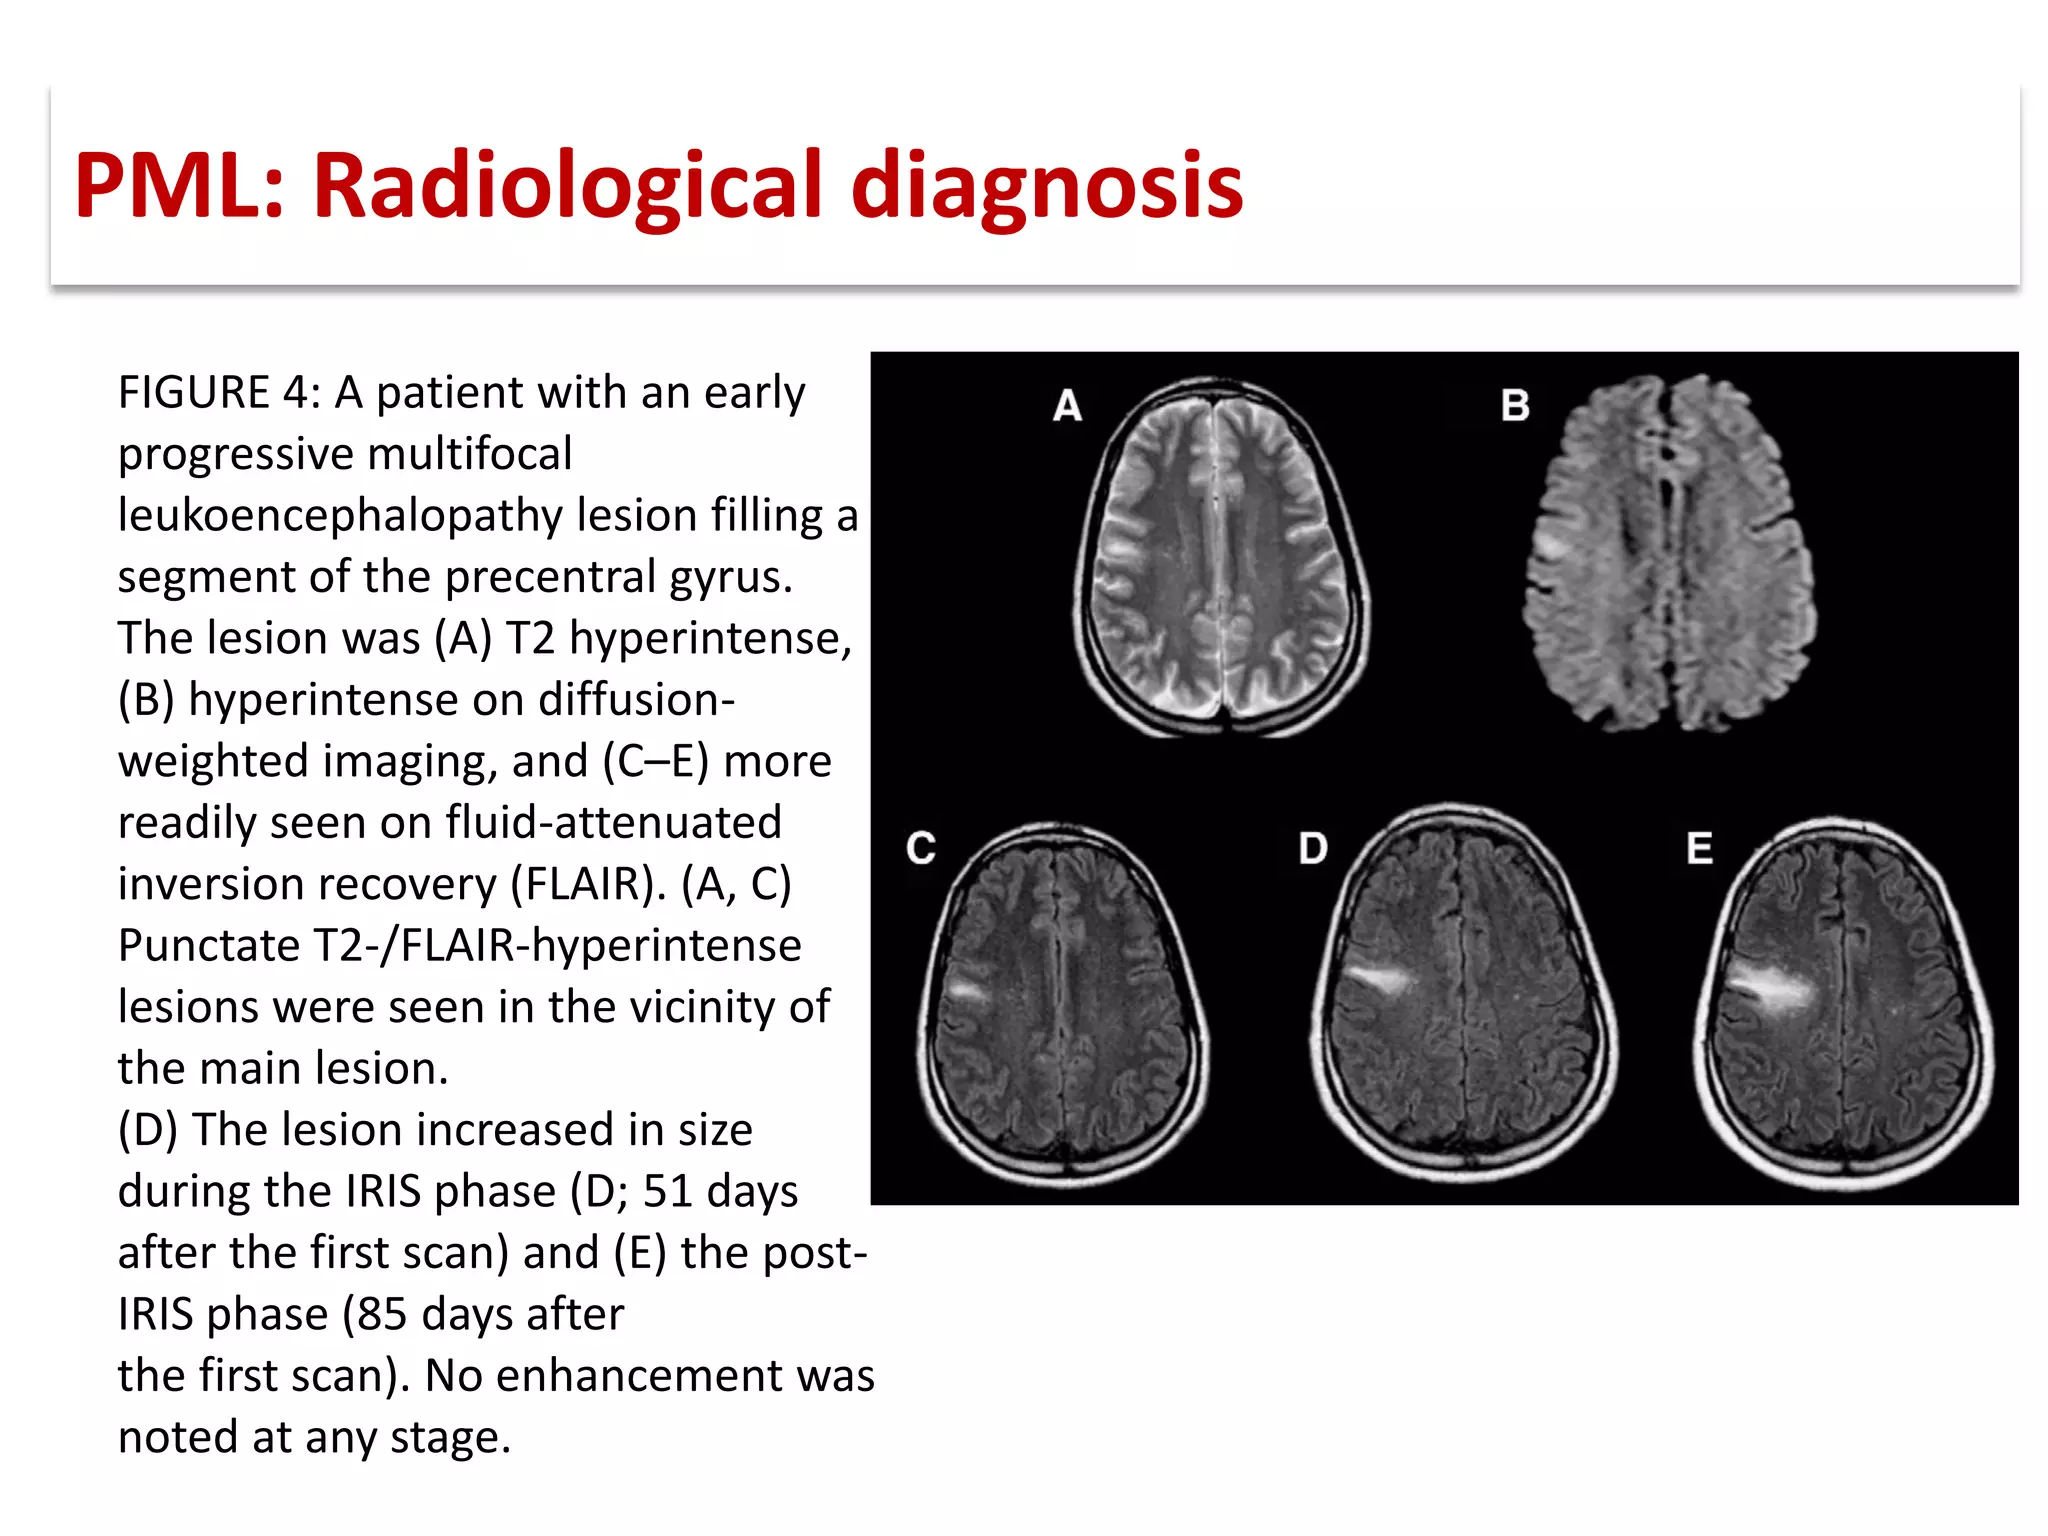

This document discusses progressive multifocal leukoencephalopathy (PML), an opportunistic infection caused by the John Cunningham virus (JCV) that leads to demyelination in the central nervous system. It highlights the epidemiology, clinical manifestations, diagnostic methods, and risk factors associated with PML, particularly in immunocompromised patients and those undergoing immunomodulatory therapies. It also presents data on the incidence of PML in patients treated with natalizumab and other therapies, addressing the relationships between these treatments and the development of PML.